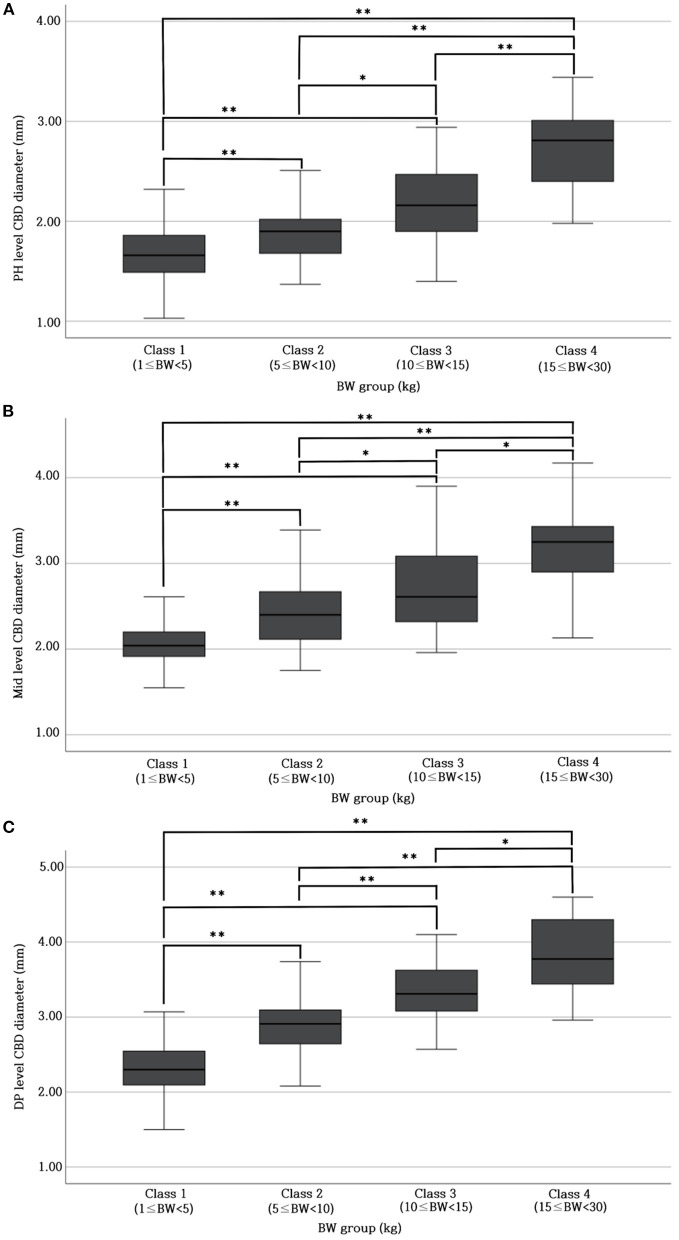

The reference range of CBD diameter at PH level: 1.69 ± 0.29 mm (Class 1; 1 kg ≤ BW < 5 kg), 1.92 ± 0.35 mm (Class 2; 5 kg ≤ BW < 10 kg), 2.20 ± 0.43 mm (Class 3; 10 kg ≤ BW < 15 kg), 2.79 ± 0.49 mm (Class 4; 15 kg ≤ BW < 30 kg); Mid-level: 2.06 ± 0.25 mm (Class 1), 2.43 ± 0.37 mm (Class 2), 2.74 ± 0.52 mm (Class 3), 3.14 ± 0.44 mm (Class 4); DP level: 2.33 ± 0.34 mm (Class 1), 2.90 ± 0.36 mm (Class 2), 3.35 ± 0.49 mm (Class 3), and 3.83 ± 0.50 mm (Class 4). There was a significant difference in CBD diameter at each level among all BW groups. Furthermore, BW and CBD diameter showed positive linear correlation at each level. We devised CBD: Ao ratio at each level that showed no significant difference between the different BW groups; PH level: 0.34 ± 0.05; Mid-level: 0.42 ± 0.06; DP level: 0.47 ± 0.06.

Table 1 provides the normal reference range and upper limit of the CBD diameters at each level for each BW group. The CBD diameter at each level differed significantly (p < 0.05* or p < 0.001**) among all BW groups (Figures 2A–C).

Table 1: Values of normal reference range of CBD at PH, Mid, and DP level for different BW groups.

| BW (kg) group | Number | CBD diameter Mean ±SD (mm) | 95% reference intervals upper limit (mm) | ||||

|---|---|---|---|---|---|---|---|

| PH | Mid | DP | PH | Mid | DP | ||

| Class 1 (1 ≤ BW < 5) | 119 | 1.69 ± 0.29 | 2.06 ± 0.25 | 2.33 ± 0.34 | 1.74 | 2.10 | 2.39 |

| Class 2 (5 ≤ BW < 10) | 99 | 1.92 ± 0.35 | 2.43 ± 0.37 | 2.90 ± 0.36 | 1.99 | 2.51 | 2.97 |

| Class 3 (10 ≤ BW < 15) | 35 | 2.20 ± 0.43 | 2.74 ± 0.52 | 3.35 ± 0.49 | 2.35 | 2.92 | 3.52 |

| Class 4 (15 ≤ BW < 30) | 30 | 2.79 ± 0.49 | 3.14 ± 0.44 | 3.83 ± 0.50 | 2.97 | 3.31 | 4.02 |

BW, body weight; CBD, common bile duct; DP, duodenal papilla; Mid, mid-portion; PH, porta hepatis; SD, standard deviation.